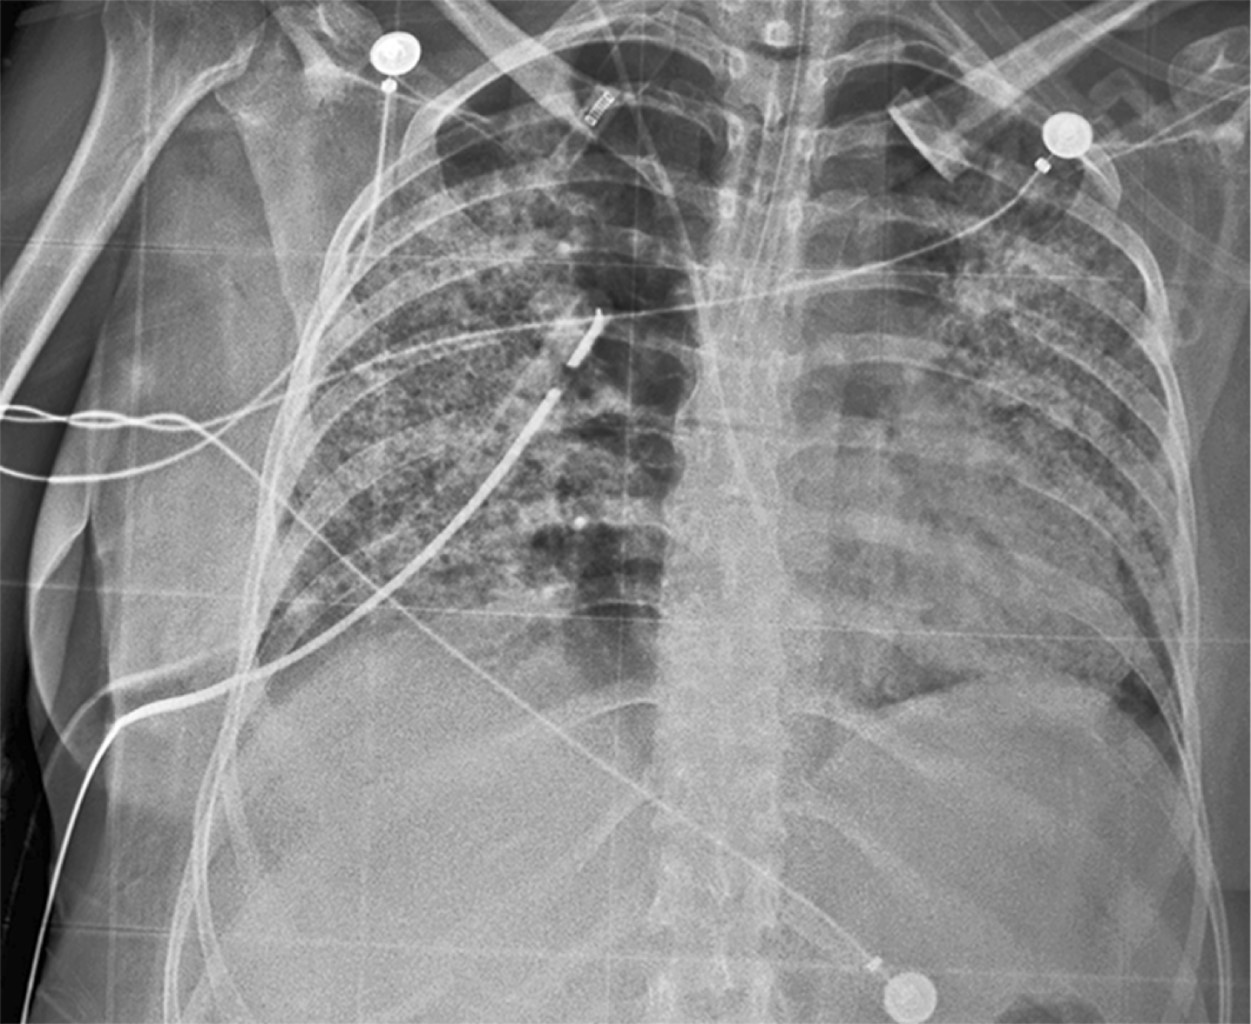

Granulomatosis with polyangiitis is a rare and serious autoimmune condition. In addition to typical symptoms, some patients may present invasion of the central nervous system, manifested as central diabetes insipidus. However, this complication occurs in less than 1%, making it a diagnostic challenge. We report the case of a 33-year-old patient previously diagnosed with granulomatosis with polyangiitis following a bout of alveolar hemorrhage, who started treatment with azathioprine and prednisone. Upon tapering off prednisone, she developed temporal headache, polyuria, and polydipsia. We present the diagnostic approach of a patient with the main clinical feature of polyuria. The presentation of cases with atypical progression is essential to improve understanding and management of this rare but significant condition in the context of granulomatosis with polyangiitis.

Figure 1